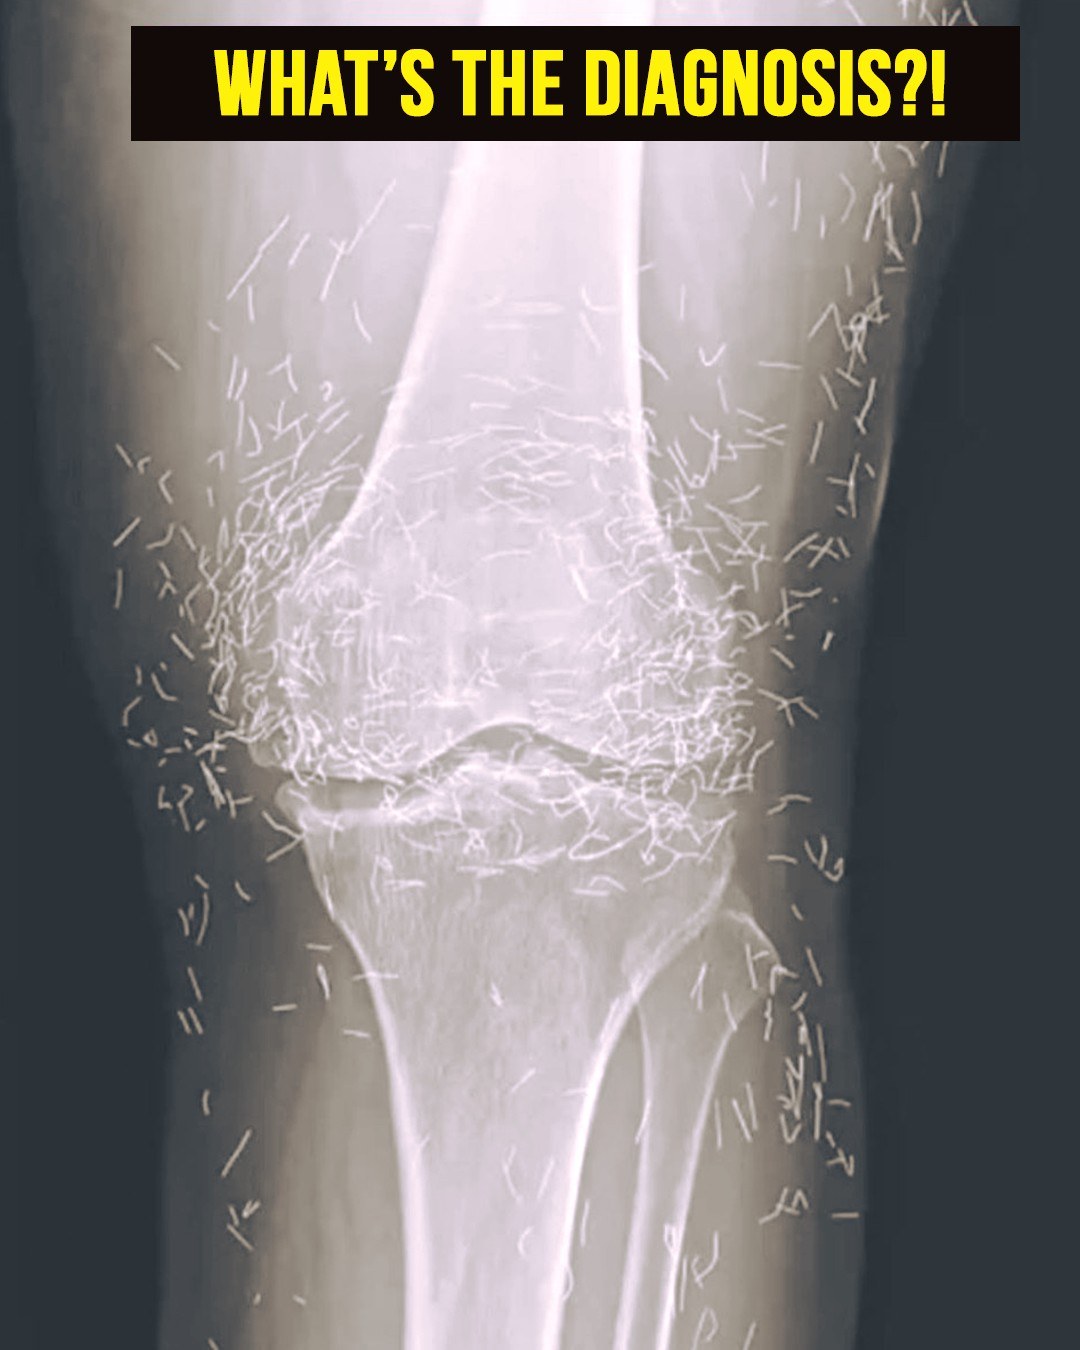

In this woman’s case, imaging studies revealed multiple gold needles embedded deep within her knee joints. Radiologists were surprised by the density and number of retained objects, which created both clinical interest and concern.

In her case, the needles—believed to be gold—were left inside her knees intentionally. This practice, known as intradermal or retained acupuncture, is intended to provide continuous stimulation to the joint and prolong therapeutic effects.

In South Korea, inserting tiny sterile gold threads around a joint is a traditional treatment for osteoarthritis. This method is thought to stimulate blood flow, promote healing, and reduce pain, although rigorous scientific validation is still lacking.

Modern imaging techniques, including X-rays and MRIs, can detect these embedded needles. Radiologists must consider retained metal when interpreting images, as it can interfere with diagnostic clarity and obscure underlying conditions.